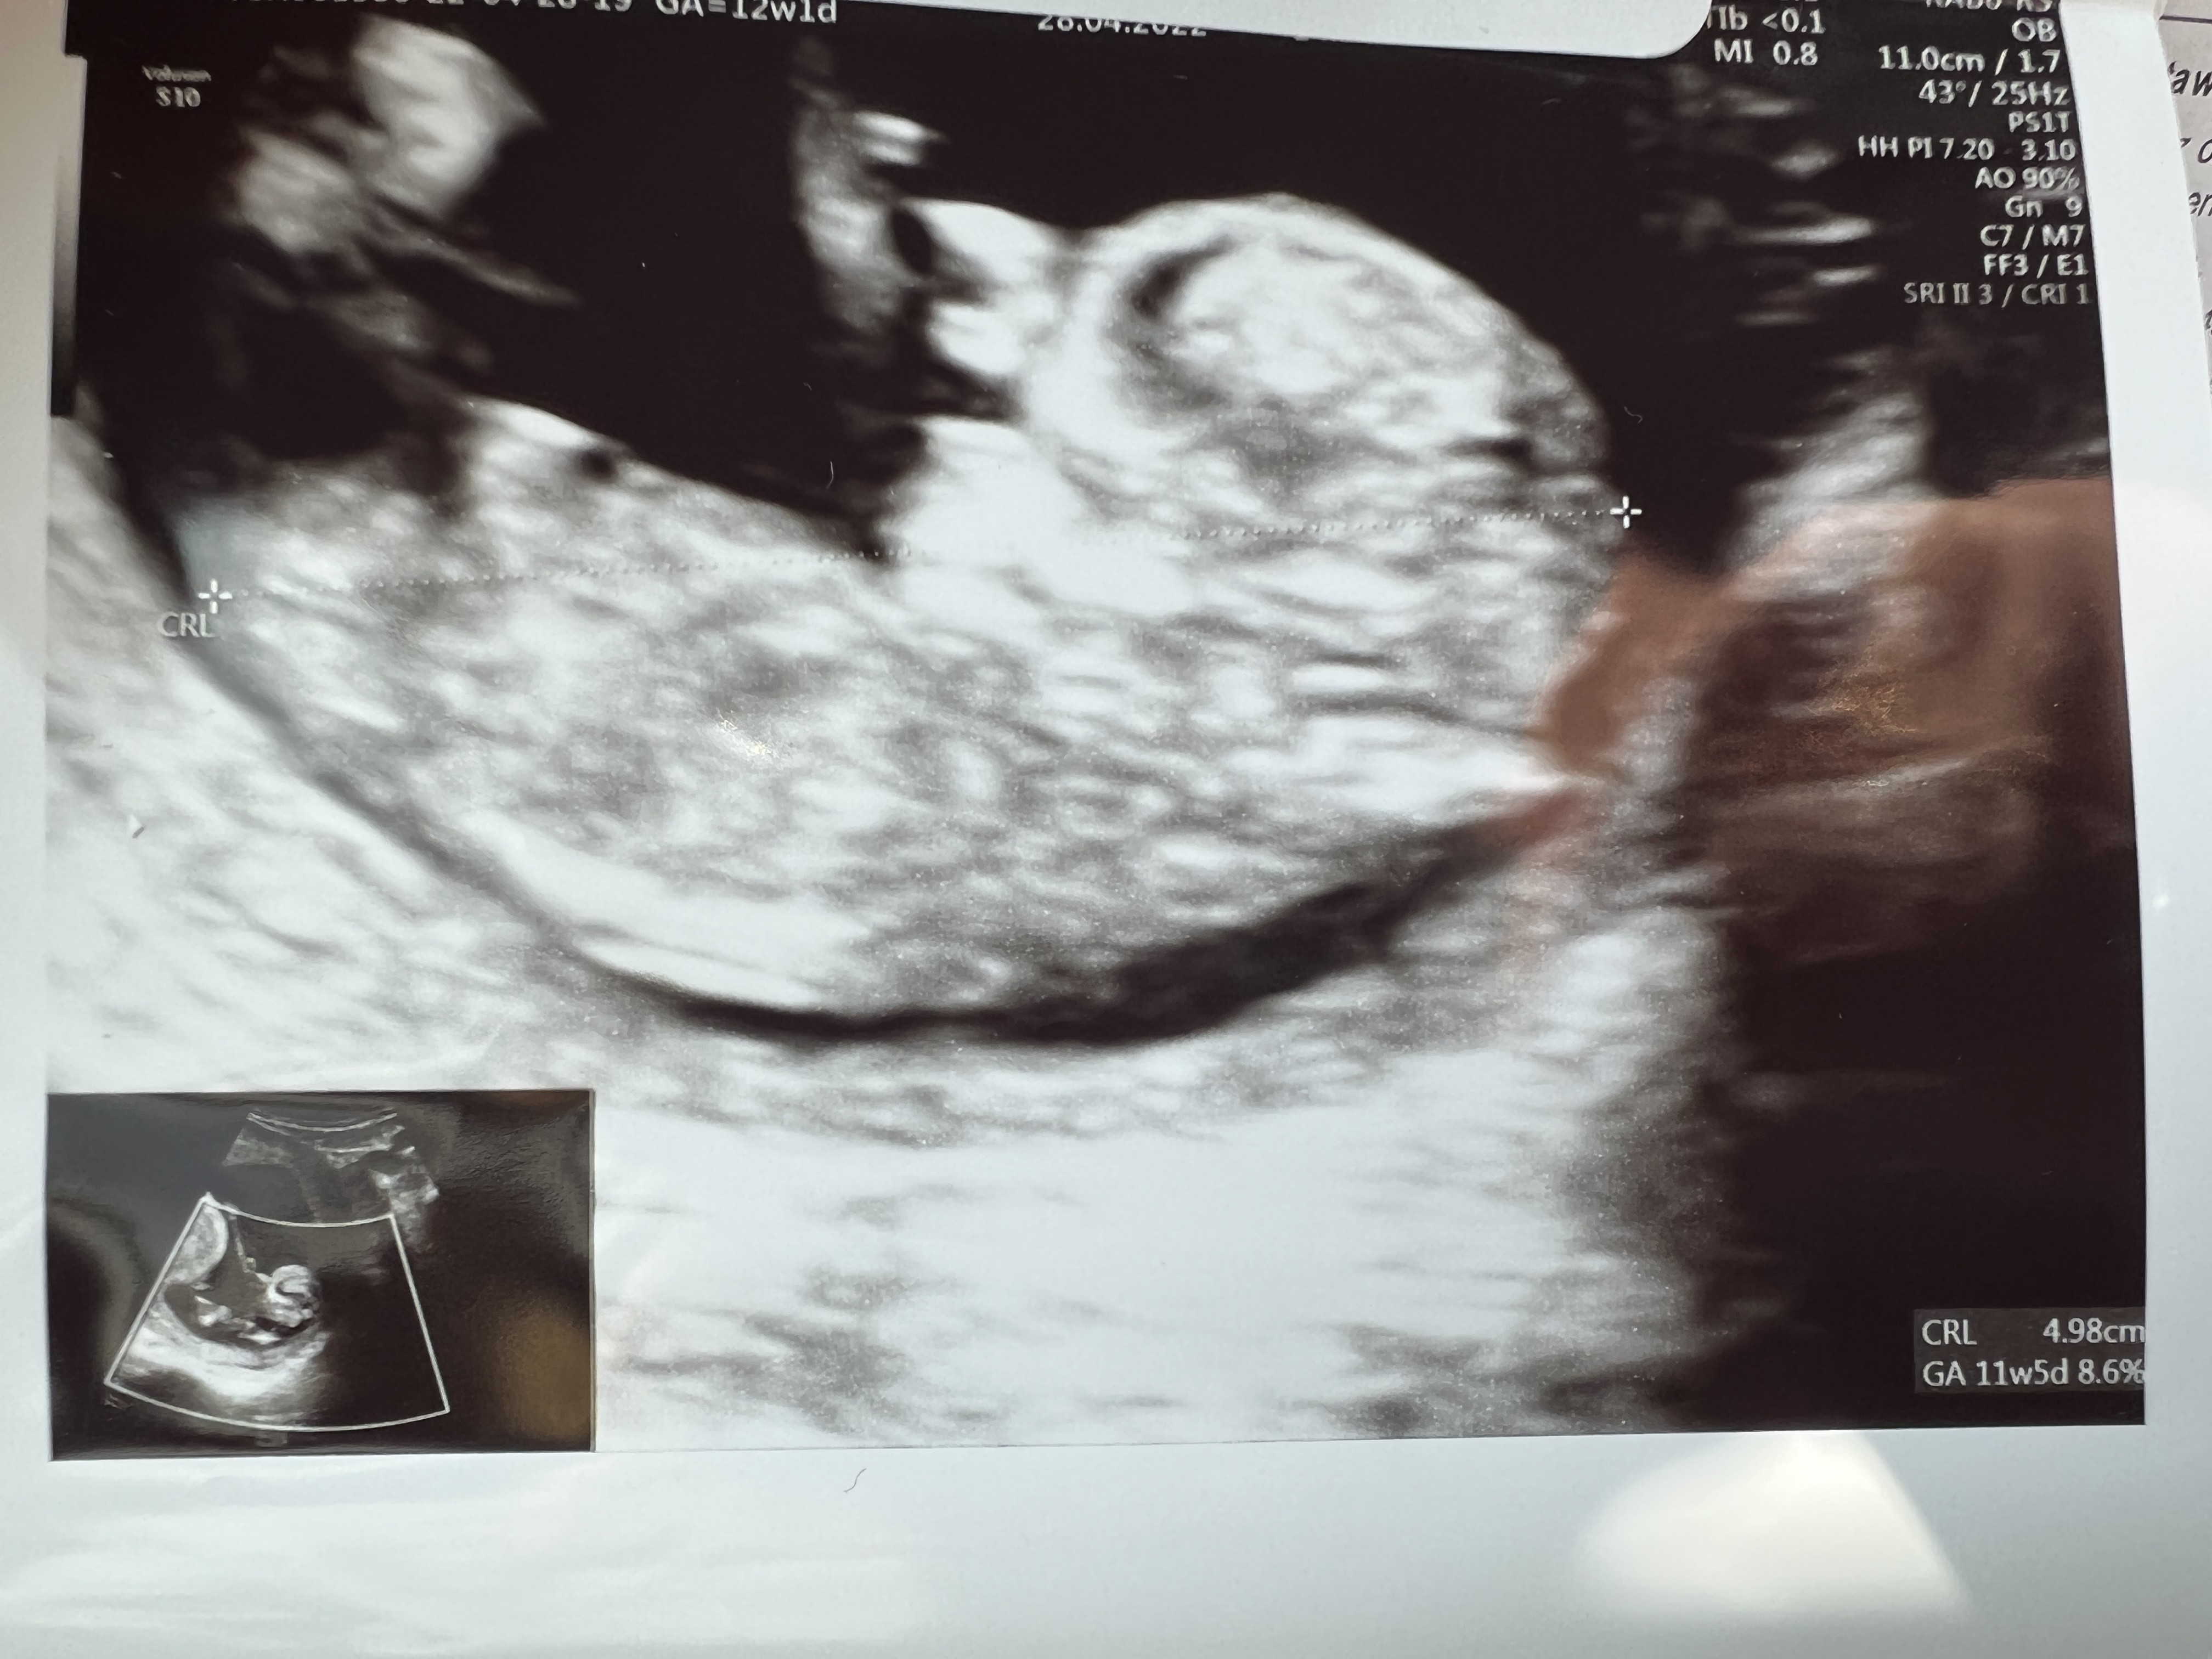

@Aleksandrettasuper wieści. Jak ja Cię rozumiem z tą lekkością 🥰. Ja też od mojego wyszłam kg kilo lżejsza i szczęśliwa. Dzidziol ma 4.3 cm, kość nosowa pięlnie widać, przezierność karkową również, raczki nóżki też. Kazał mi być spokojną i wiecej powiedzą na prenatalnych. Aaaa i prawdopodobnie siusiak ;).